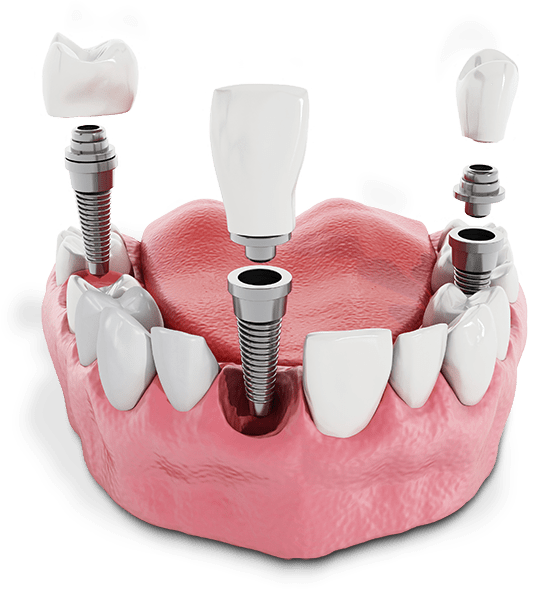

Texas Center for Oral Surgery and Dental Implants is known throughout the area for offering a variety of dental implant solutions. These include single, immediate dental implants, implant-supported dentures, and full-arch dental implants. Set up a consultation today to find out which type of dental implant will work best to restore your smile.

An oral surgeon is a special type of dental professional who has gone to school for extra years. Oral surgeons are experts in all types of oral surgery. This makes them the perfect choice if you need placement of dental implants or have had a facial trauma that requires surgical attention.

When it comes to choosing the right healthcare provider, credentials and experience always matter. Having an oral surgeon place your dental implants gives you tremendous peace of mind and lowers the chance of dental implant failure.

Wisdom tooth extractions are different procedures than normal tooth extractions. Therefore, you’ll want to put your care into the hands of someone who has the equipment and knowledge to address even the toughest issues.